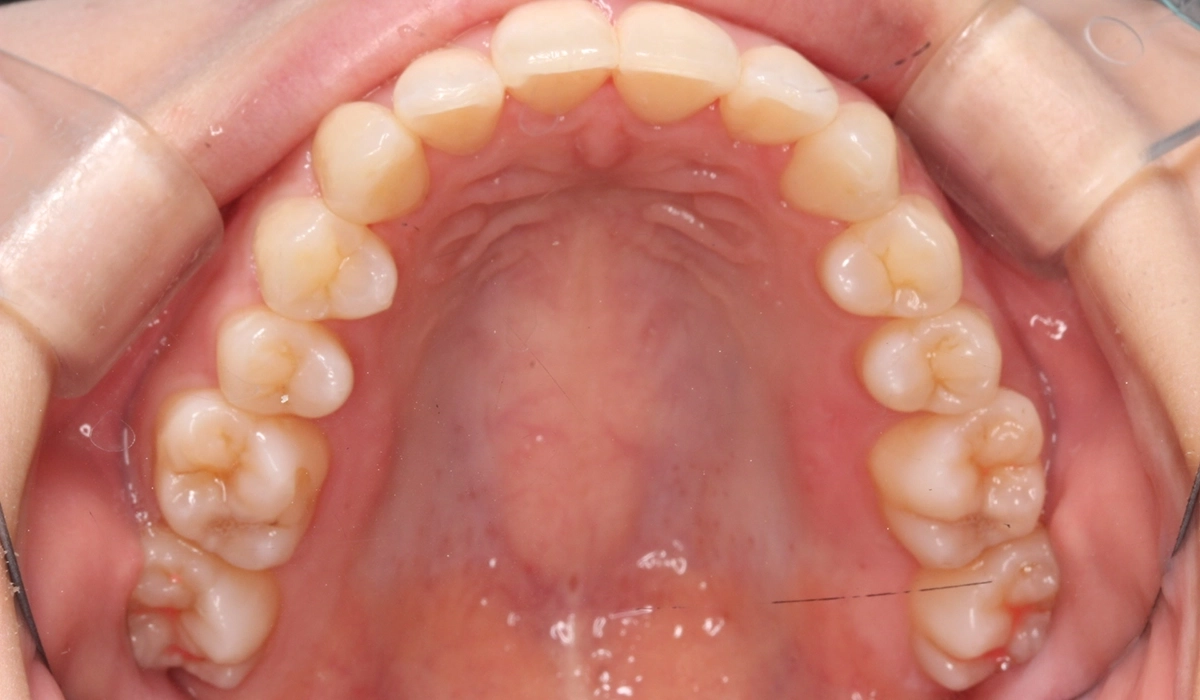

術前:下顎

術後:下顎